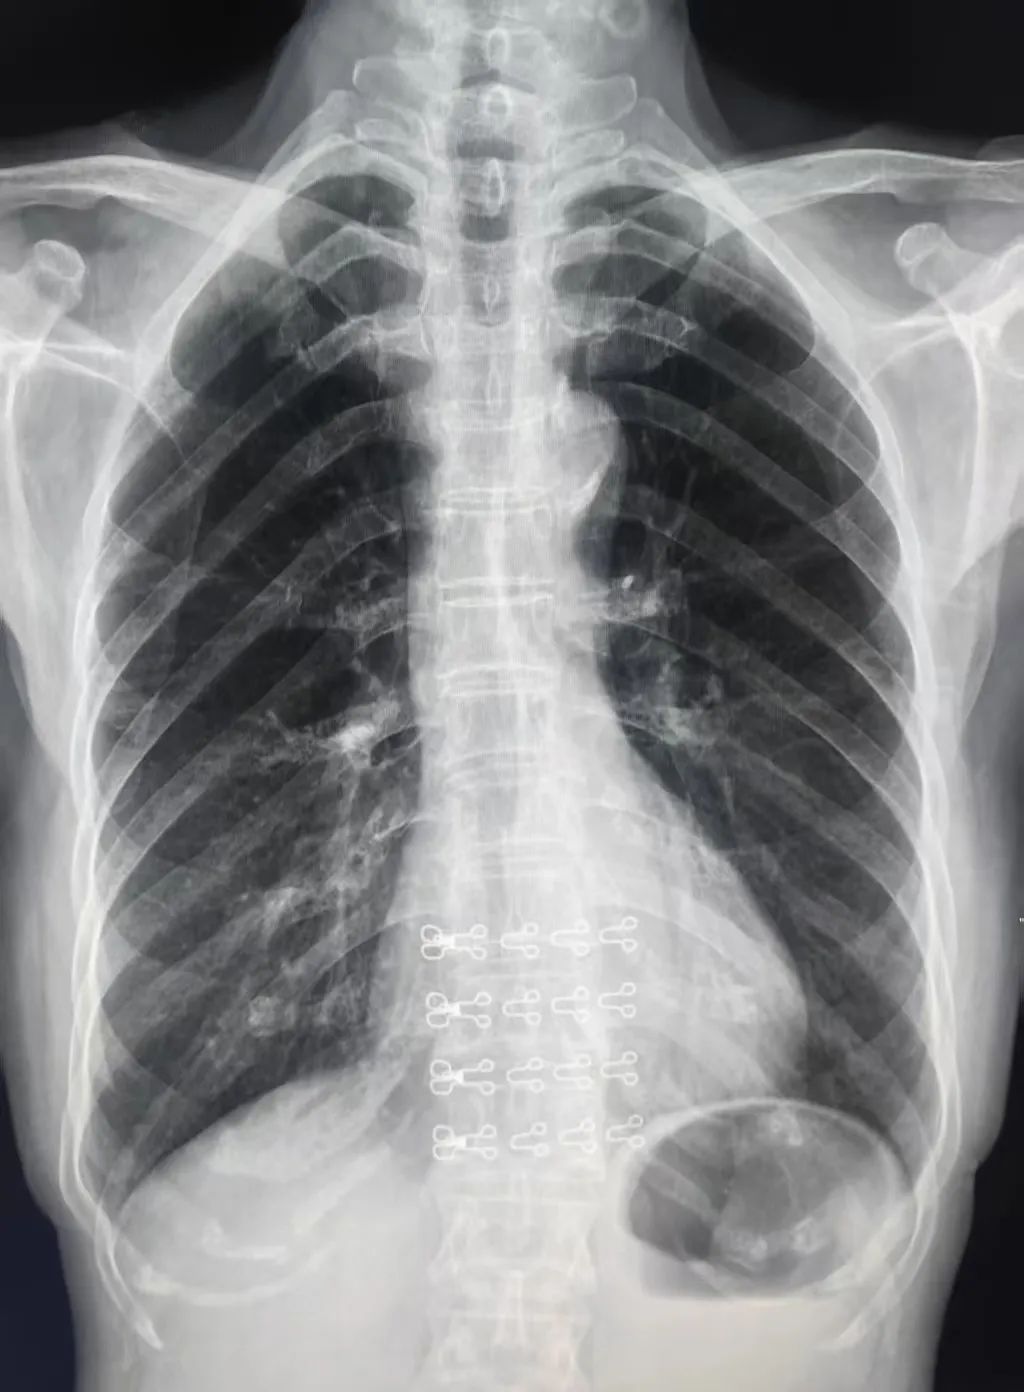

1.常规X光检查:①胸部X光:用于诊断肺炎、肺结核、肺癌等肺部疾病,同时也能观察心脏的形态和位置;